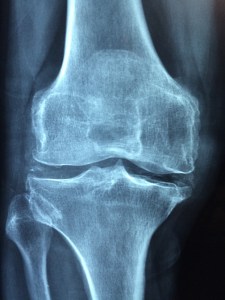

I had a total knee replacement two days ago. It isn’t as much fun as it sounds.

Image of X-ray by Dr. Manuel González Reyes from Pixabay